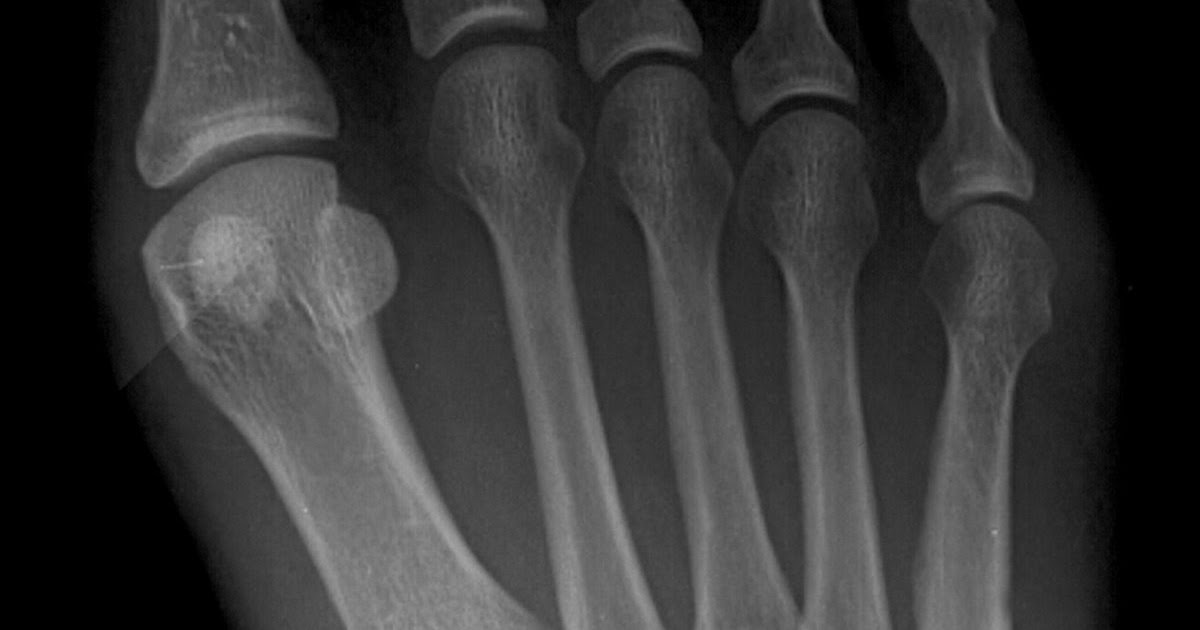

Metatarsal Fractures Nana O. Sarpong, Hasani W. Swindell, Evan P Hairline Fracture Ankle Boot In some cases, an orthopedic surgeon may need to use pins,. Causes and symptoms of foot hairline fractures. Hairline fractures, also sometimes referred to as stress fractures, involve the development of tiny cracks or bruises in the bone. In most cases, this requires a special boot or a cast. The doctor will inspect the injured area and, likely, apply. Diagnosing. Hairline Fracture Ankle Boot.